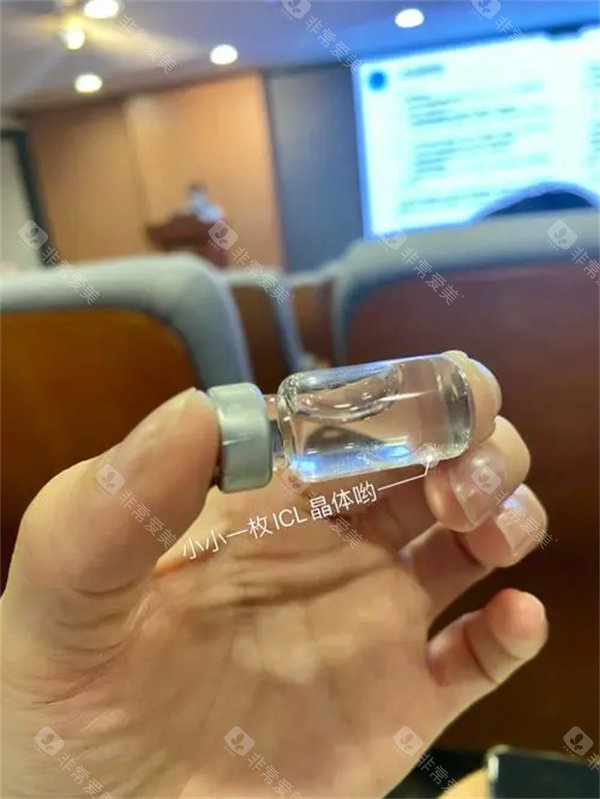

ICL晶体植入手术作为高度近视矫正的主流方案,凭借其可逆性、不损伤角膜的特点,成为越来越多近视患者的选择。

根据2025年爱尔眼科国内分院的收费标准,ICL晶体植入手术主要分为基础型ICL、散光矫正型TICL和飞秒辅助ICL三类,价格区间如下:

晶体类型:EVO V5比V4c贵3000~5000元,散光矫正型比基础型贵4000~6000元。